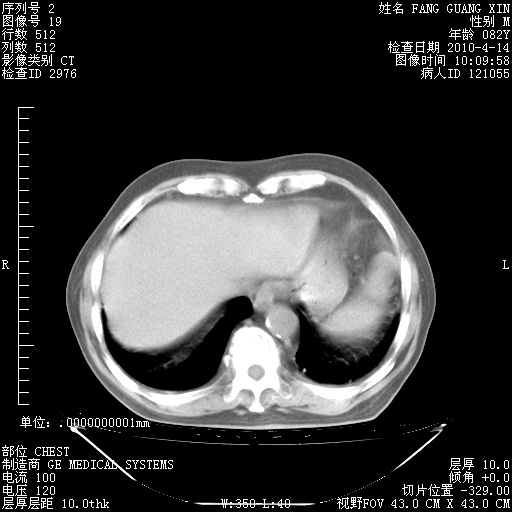

4月14日肺部CT

肺部CT平扫未见异常。